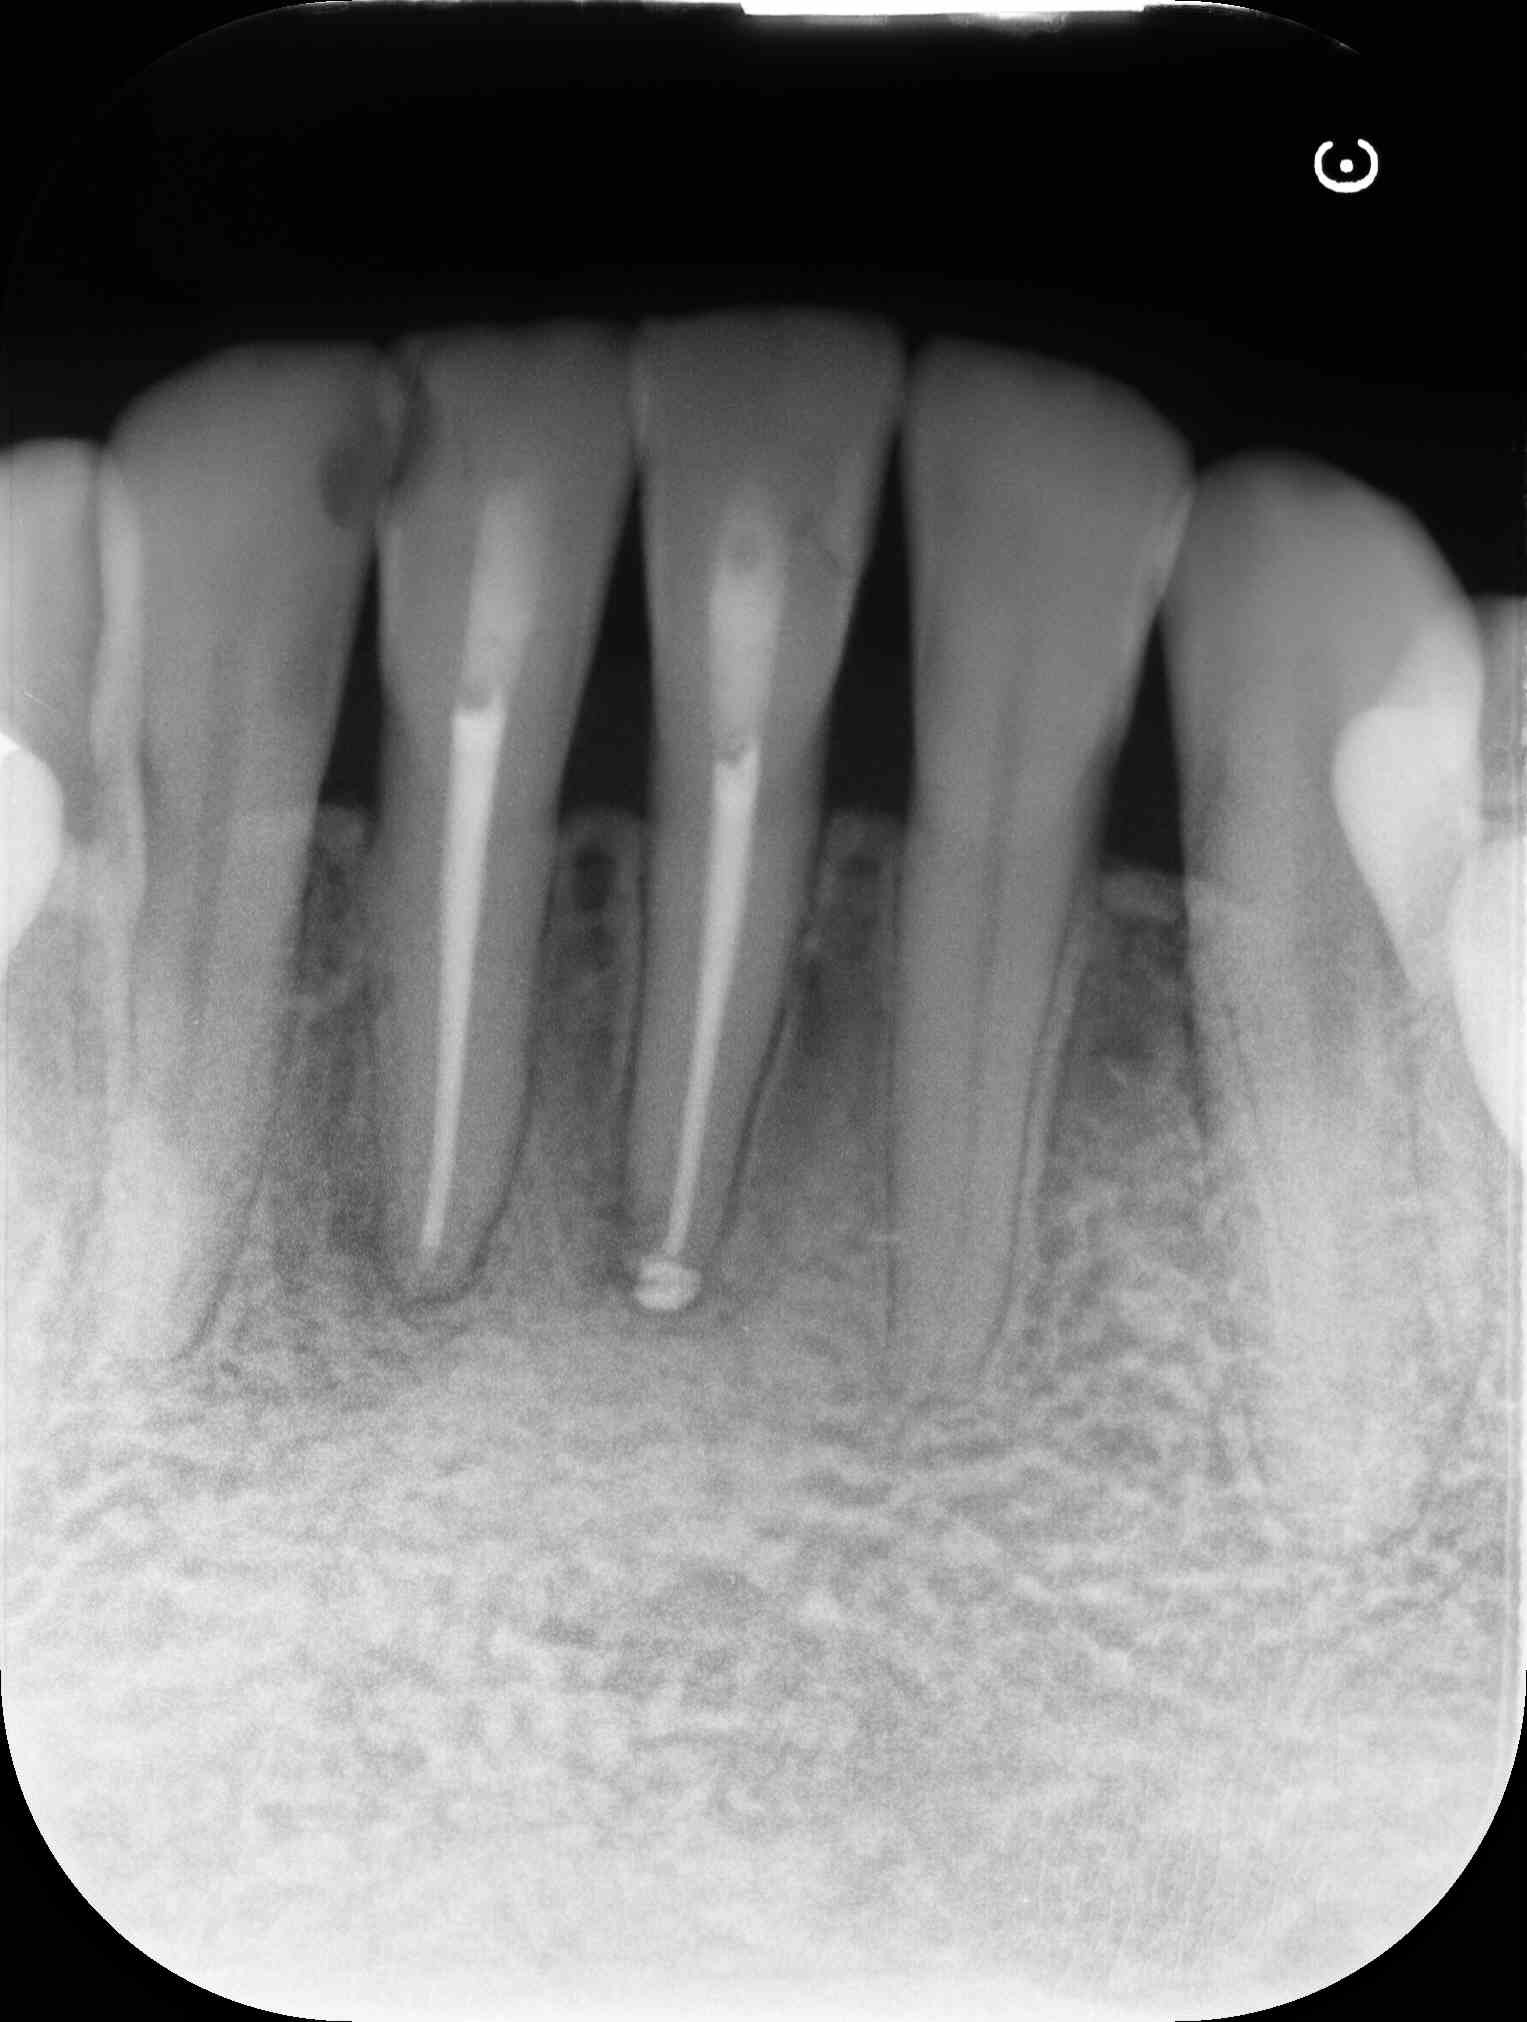

術前のレントゲン写真とCT画像と、お口の中の写真です。下の前歯2本(#31,41)です。

2本の根の周りに黒い影(透過像)があるのが分かります。

術直後のレントゲン写真です。

術後6ヵ月後のレントゲン写真とCT画像です。

術前にあった根の周りの黒い影は縮小して改善しているのが分かります。